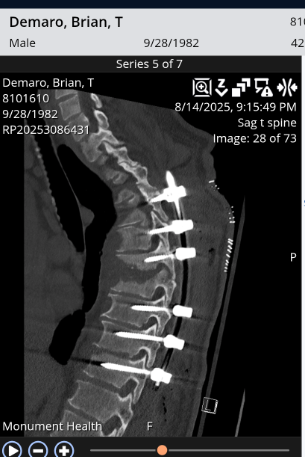

By the time it was discovered, the infection had already caused significant damage. For nearly three months, it was misdiagnosed, allowing it to spread. When Brian finally received an MRI, the doctors told him to go immediately to the ER. The infection had eaten away at multiple areas of his spine, and one wrong move could have left him paralyzed.

He must wear a brace at all times (except when sleeping or showering) to support his spine, which is now held together with screws and rods. He’s on IV antibiotics 24/7 for 12 weeks through a PICC line, after which he will be on oral antibiotics for weeks to months. He has to use a bone stimulator daily and will have to go through physical therapy once his doctors deem it safe to remove his brace, which won't be for some time. His activity is extremely limited, and he continues to attend frequent doctor appointments.